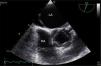

A 38-year-old female liver donor candidate was referred to our cardiology clinic for preoperative evaluation. The patient had no symptoms. On physical examination, a grade 2/6 early diastolic murmur was heard at the third left sternal intercostal space. Her blood pressure was 140/70 mmHg. Transthoracic echocardiography revealed moderate aortic regurgitation (AR) with the suspicion of quadricuspid aortic valve (QAV). Left ventricular end-diastolic and end-systolic diameters were 5.6 cm and 4.0 cm, respectively. Ejection fraction was normal. Transesophageal echocardiography confirmed the diagnosis of QAV with four equal cusps (Type A) (Figures 1 and 2, Video 1) with moderate AR (Figure 3). The patient was removed from the donor list with a suggestion for regular outpatient cardiology clinic visits.